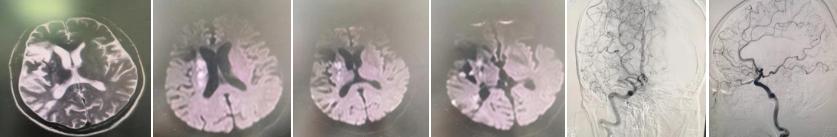

到达急诊,陈医生详询病史仔细查体,患者左侧面舌瘫,左上肢已经0级(不能活动),左下肢III级(站立困难)。NHISS评分:9分,MRS评分:5分。患者头CT已经显影,且是左侧额、颞,枕大面积低密度梗死灶。此时家属描述4个月前曾因脑梗发病接受过治疗,出院后生活工作恢复正常。陈磊医生比照既往住院头CT,考虑为陈旧病灶,此次责任病灶没有显影,确定急性脑梗死。立即决定给予入院溶栓治疗。溶栓后6小时,患者症状较之前有所缓解,左上肢II级(轻微上抬),左下肢IV级,仍言语不清。NIHSS评分:7分,MRS:4分。予急查头MRI+DWI+头颈MRA提示多发性脑梗死,脑动脉狭窄,右侧大脑中动脉重度狭窄或闭塞。

考虑到患者仅4个月发病两次,为更明确患者血管病变程度,消除患者焦虑情绪,在征得患者及家属同意后,姚广明医生为患者行脑血管造影术。造影确诊患者右侧大脑中动脉闭塞,但患者两根大脑前动脉共干,通过眼动脉,大脑前动脉通过软脑膜代偿右侧大脑半球血供很好,不需要再次手术,患者可以安心出院。

姚广明介绍,全脑血管造影术(DSA)是诊断脑血管病变的“金标准”,全脑血管造影术(DSA)是通过股动脉穿刺置入动脉鞘,通过该动脉鞘管选用不同导管,在导丝引导下,选进所要显示动脉,注入含碘造影剂。造影剂所经过的血管轨迹连续摄片,通过电子计算机辅助成像为脑血管数字减影造影(DSA)。它可以直观地测定血管狭窄程度和范围,观察侧支循环情况;所显示的病变更为直观,在判断病变供应动脉的来源、数量、引流静脉的去向、病变血管的狭窄程度以及动脉瘤、动静脉畸形的定位定性诊断等方面,优于其他影像学检查,如超声、经颅多普勒、磁共振血管成像(MRA)、螺旋CT血管成像(CTA)、磁共振静脉血管成像(MRV)、CT灌注成像(CTP)等多种方法。